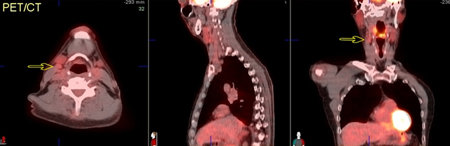

[Figure caption and citation for the preceding image starts]: 60-year-old man with squamous cell carcinoma of the right tongue base. PET/CT images show mild increased metabolism in a mid right neck lymph node, of concern for metastatic involvement (arrows)From the collection of Dr Fabio Almeida; used with permission [Citation ends].

[Figure caption and citation for the preceding image starts]: 60-year-old man with squamous cell carcinoma of the right tongue base. Axial images further caudally show extent of tumour involvement in the hypopharynx, including invasion through the hyoid boneFrom the collection of Dr Fabio Almeida; used with permission [Citation ends].